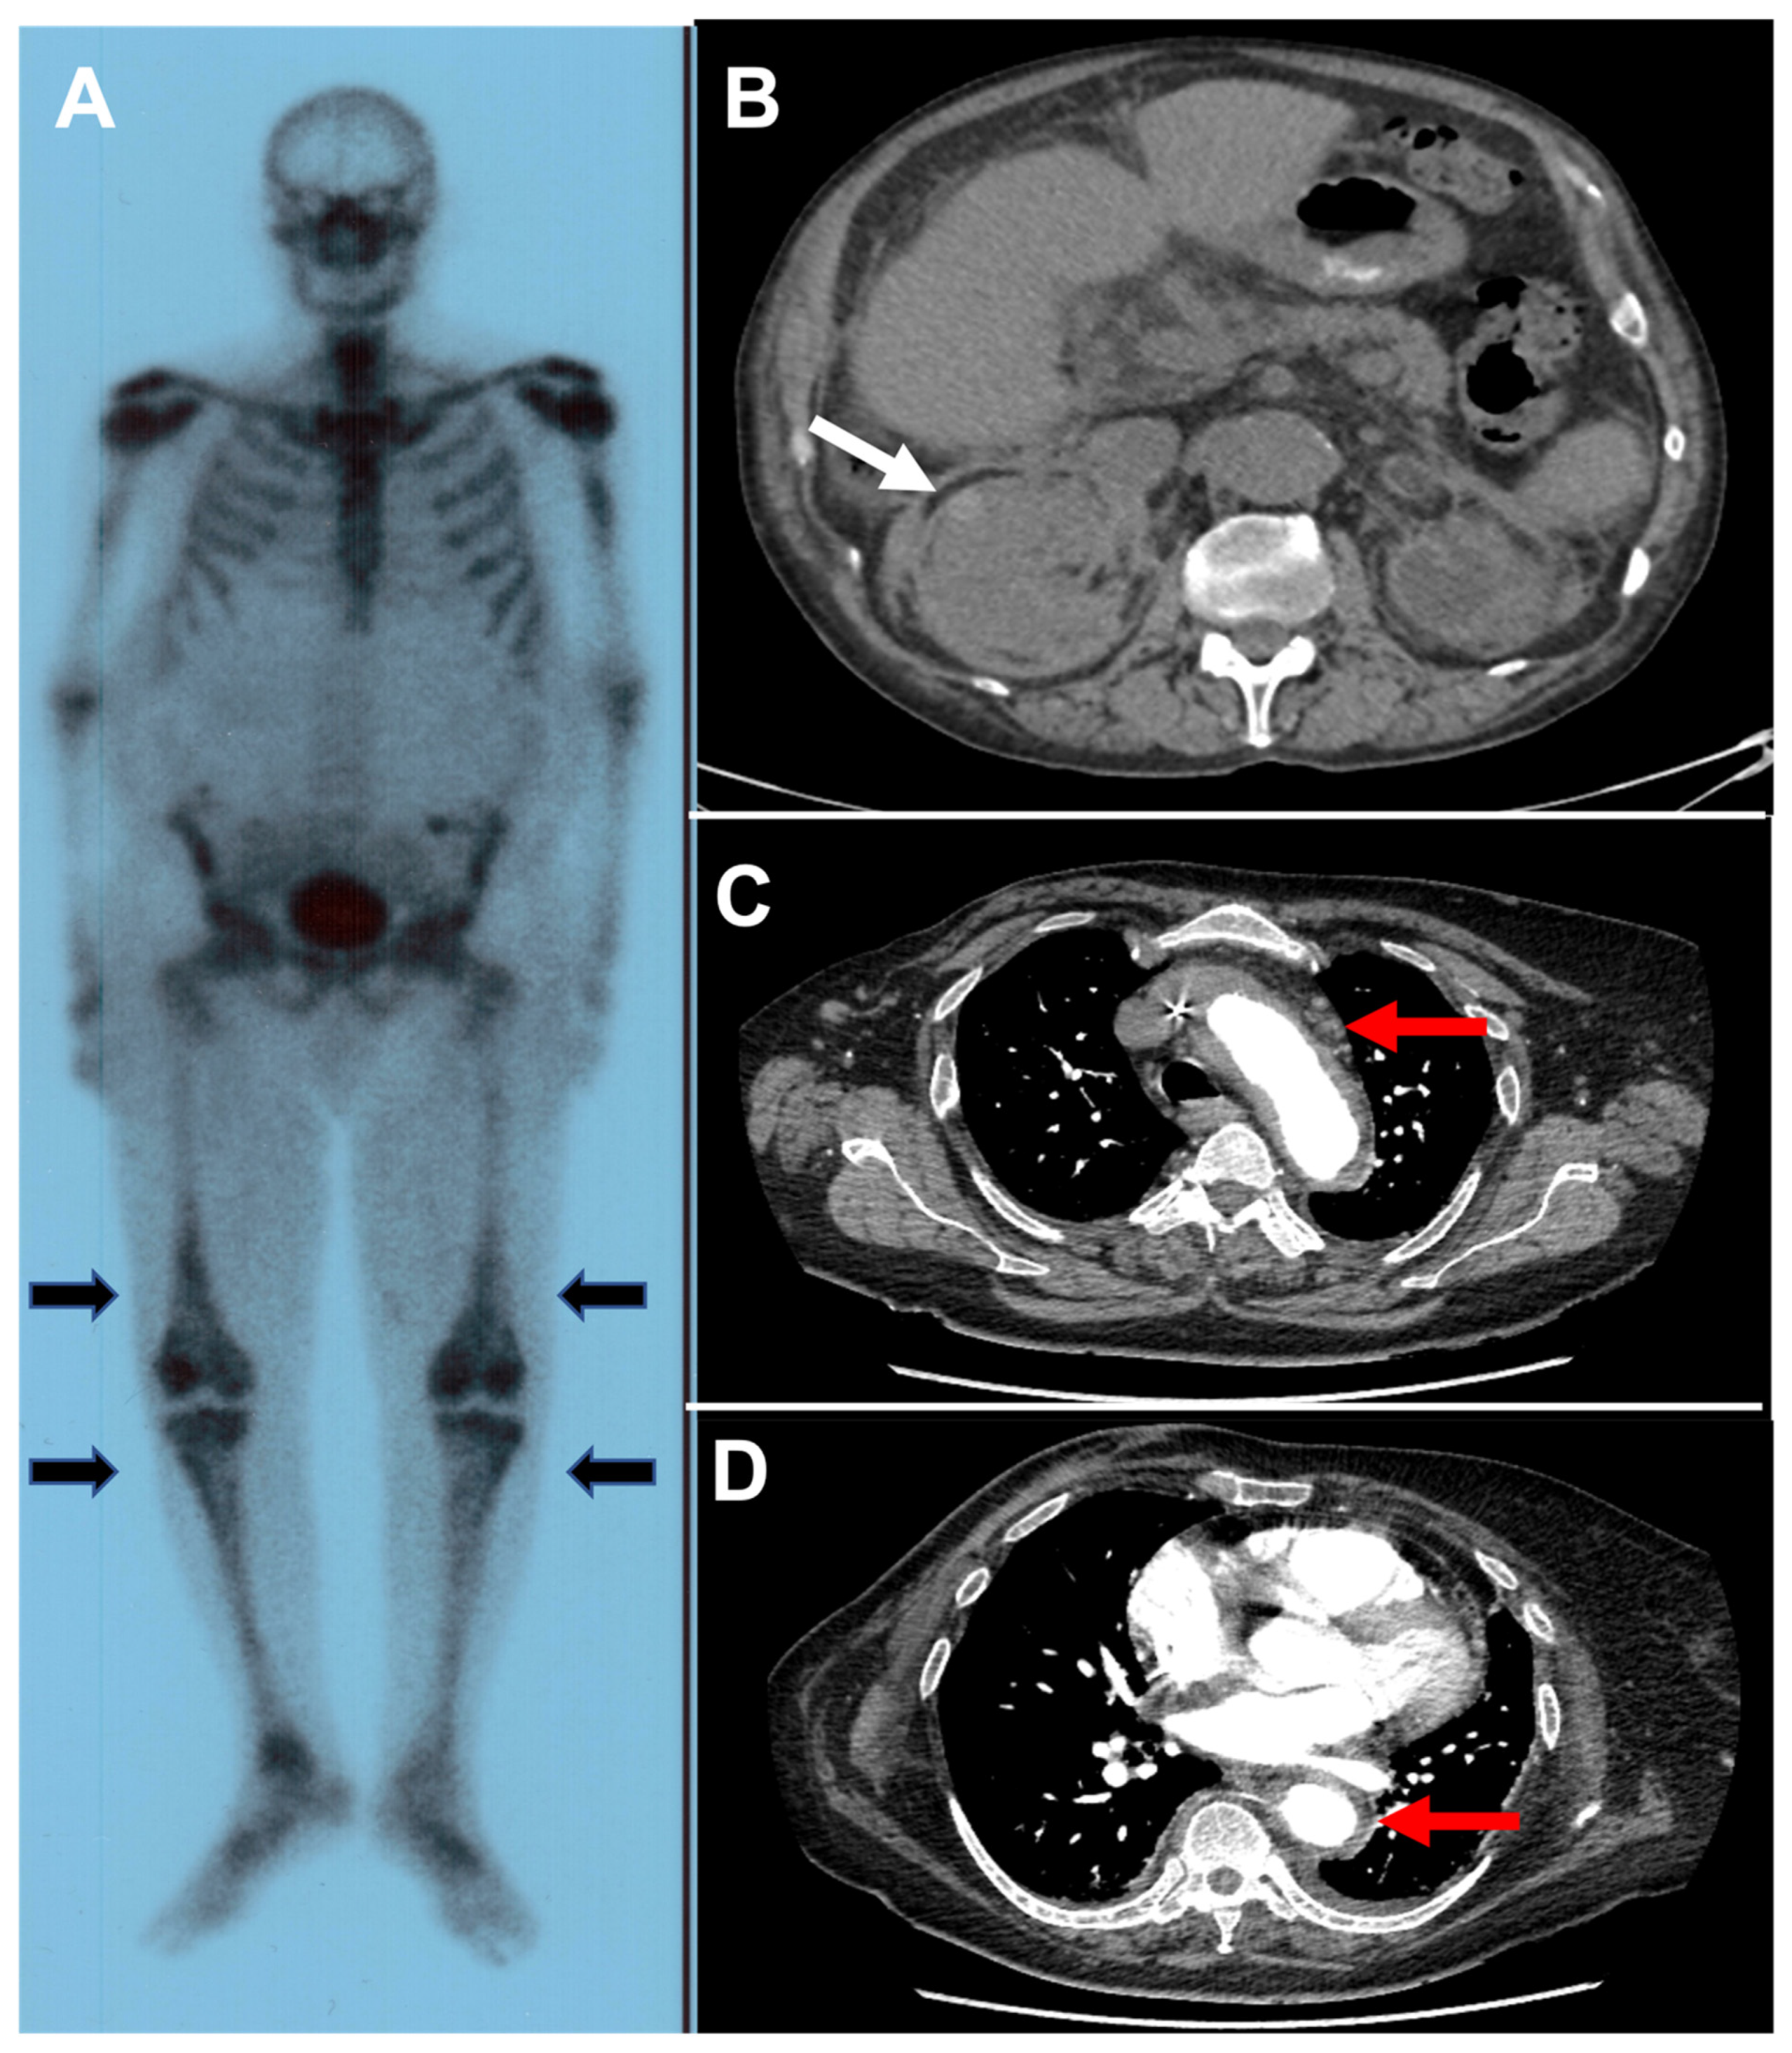

| Erdheim Chester disease | Cardiac involvement: pericarditis, right atrial pseudotumor, coronary infiltration Pulmonary involvement: interstitial lung disease, pleural infiltration Arterial disease: coated aorta Bone damage: osteosclerosis of long bones, bone pain Skin involvement: periorbital xanthelasma, papulo-nodular rash Renal involvement: hydronephrosis, hairy kidneys, retroperitoneal fibrosis Endocrinological disorders: diabetes insipidus, growth hormone deficiency, hyperprolactinemia Neurological impairment: pyramidal syndrome, cerebellar syndrome, epilepsy, headache, cognitive disorders | Foamy histiocytes CD68+CD163+FXIIa+CD1a- BRAFV600E (57% to 70%) Increased ESR and CRP |